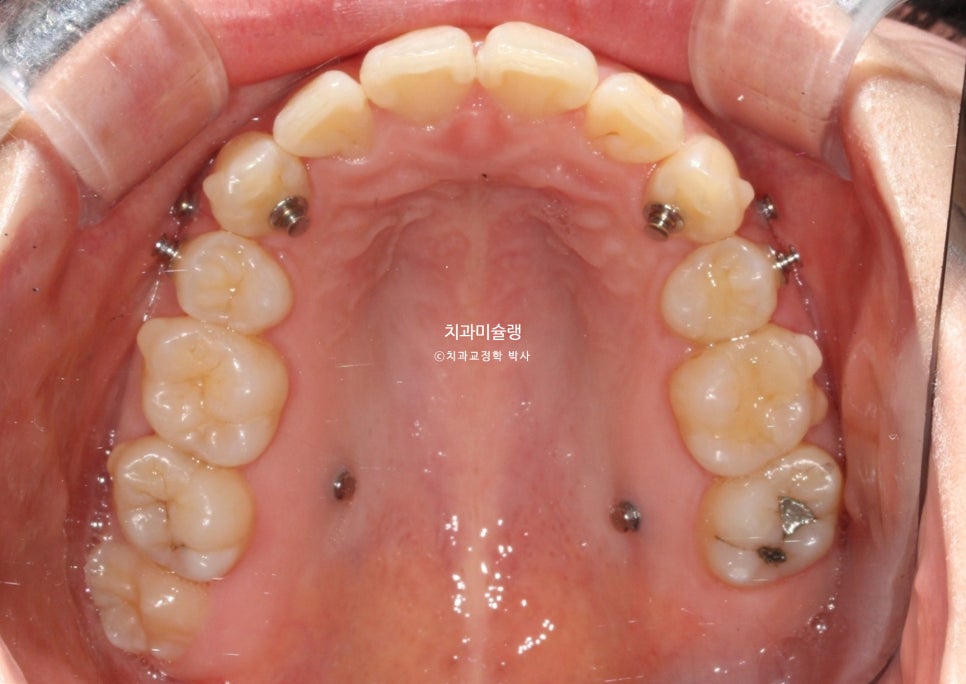

어쨎든 두번째 세트에서는 앞니 교합이 깊어짐을 방지하고 어금니 쓰러짐을 방지하고자 교정용 나사를 심고 뺏다꼈다 하는 고무줄 처방도 나갔습니다.

무난하게 70개 장치를 모두 낀 후 모습입니다.

약간의 과개교합이 남아있습니다. 중심선 개선이 더 필요힙니다.

어금니 교합은 좋습니다.

어금니 교합은 물샐틈 없는 1급 교합관계를 보입니다.

발치공간은 깔끔히 마무리 되었습니다.